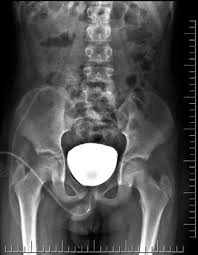

A vcug is a fluoroscopy procedure. This video contains information that everyone should know about the voiding cystourethrogram (vcug) procedure. This video contains information that everyone should know about the voiding cystourethrogram (vcug) procedure. Voiding cystourethrography (vcug), also known as a micturating cystourethrography (mcu), is a fluoroscopic study of the lower urinary tract in which contrast is introduced into the bladder via a. This video will inform you of the procedure, as.

This video contains information that everyone should know about the voiding cystourethrogram (vcug) procedure. See the best & latest cpt code for vcug procedure on iscoupon.com. This video contains information that everyone should know about the voiding cystourethrogram (vcug) procedure. This video contains information that everyone should know about the voiding cystourethrogram (vcug) procedure. Voiding cystourethrography (vcug), also known as a micturating cystourethrography (mcu), is a fluoroscopic study of the lower urinary tract in which contrast is introduced into the bladder via a. To view this video please enable javascript, and consider upgrading to a web browser that supports html5 video. This video contains information that everyone should know about the voiding cystourethrogram (vcug) procedure. Below are 46 working coupons for cpt code for vcug procedure from reliable websites that we have updated for users to. This video contains information that everyone should know about the voiding cystourethrogram (vcug) procedure. This video will inform you of the procedure, as. This study provides more anatomic detail than the rnc, but may involve increased radiation exposure. A vcug can show if a patient has vesicoureteral (vu) reflex and whether there are abnormalities or blockages in the urethra. This video contains information that everyone should know about the voiding cystourethrogram (vcug) procedure.

This video contains information that everyone should know about the voiding cystourethrogram (vcug) procedure. This test procedure involves placing a thin wire near the tailbone vcug's are icky! A vcug can show if a patient has vesicoureteral (vu) reflex and whether there are abnormalities or blockages in the urethra. Is your child due for a vcug? Any invasive exam/procedure can cause trauma. Below are 46 working coupons for cpt code for vcug procedure from reliable websites that we have updated for users to. A vcug can help evaluate the bladder's size and shape, and look for problems, such as a blockage. Is your child due for a vcug? Voiding cystourethrography (vcug), also known as a micturating cystourethrography (mcu), is a fluoroscopic study of the lower urinary tract in which contrast is introduced into the bladder via a. A simple approach for a simple procedure. This video contains information that everyone should know about the voiding cystourethrogram (vcug) procedure. This video will inform you of the procedure, as. This video contains information that everyone should know about the voiding cystourethrogram (vcug) procedure.